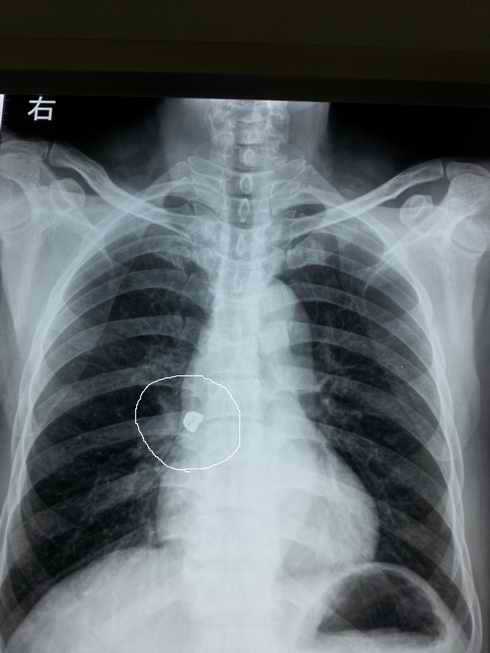

图片1:X片示右中间支气管内 异物

上周五,一位家住宁波市鄞州区横溪镇的农民因在进食时出现金属牙套松动,不慎掉入气管,当时就出现剧烈咳嗽,气促,胸闷等症状,难以忍受,痛苦不堪,当地医院紧急联系我科,我科由俞万钧副院长亲自操作,在支气管镜下经过不到20分钟,顺利取出牙套,解除患者痛苦,患者及家属感激万分。